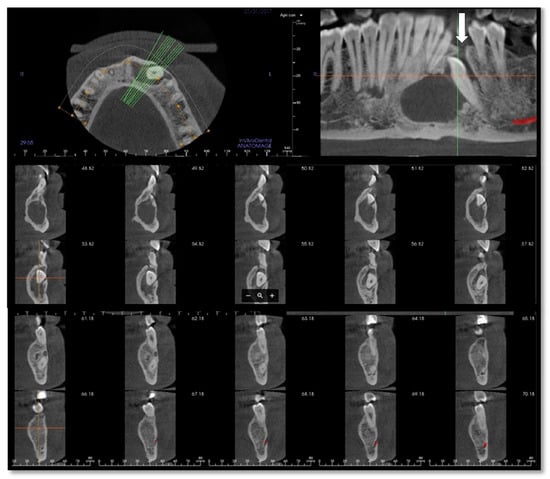

Figure 2.

Cone-beam computed tomography (CBCT) of the mandible performed in January 2017 after the first infective episode and showing no atypical radiologic findings. The osteolytic alveolar defect (white arrow) has led to the recurrent oral discharge.

The radiological appearance of PIOSCC is variable, ranging from well-defined benign-like masses to ill-defined osteolytic lesions [,]. The most common imaging presentation is a radiolucent cup or dish-shaped osteolytic bone lesion, followed by diffuse and poorly defined borders appearance known as ‘moth-eaten’ radiographic pattern []. Kaffe et al. proposed that the presence of indistinct margins without a sclerotic outline may be an important peculiarity of PIOSCC [] (Figure 2). Another significant radiograph characteristic is the lack of root resorption, presumably suggesting that the tumor invasion occurs along the path of least resistance, resulting in a unique pattern known as ‘floating-teeth,’ which is rarely seen in benign odontogenic cysts or tumors [] (Figure 2). Radiopaque foci corresponding to calcifications or dentinoid structures and ground-glass opacity (possibly mimicking fibrous dysplasia or ossifying fibroma) have also been reported by some authors [,].

In our case, orthopantomography (Figure 1) and CT (Figure 2) showed a uniloculated 38 × 14 mm osteolytic area affecting the chin symphysis and extending in the left paramedian region. The lesion interrupted the vestibular bone cortex but spared the lingual one.

MRI with gadolinium-contrast represents a second-level examination essential for tumor staging, and in our case, the extent of the lesion through the anterior cortex erosion in the soft tissues of the chin was documented (Figure 6).